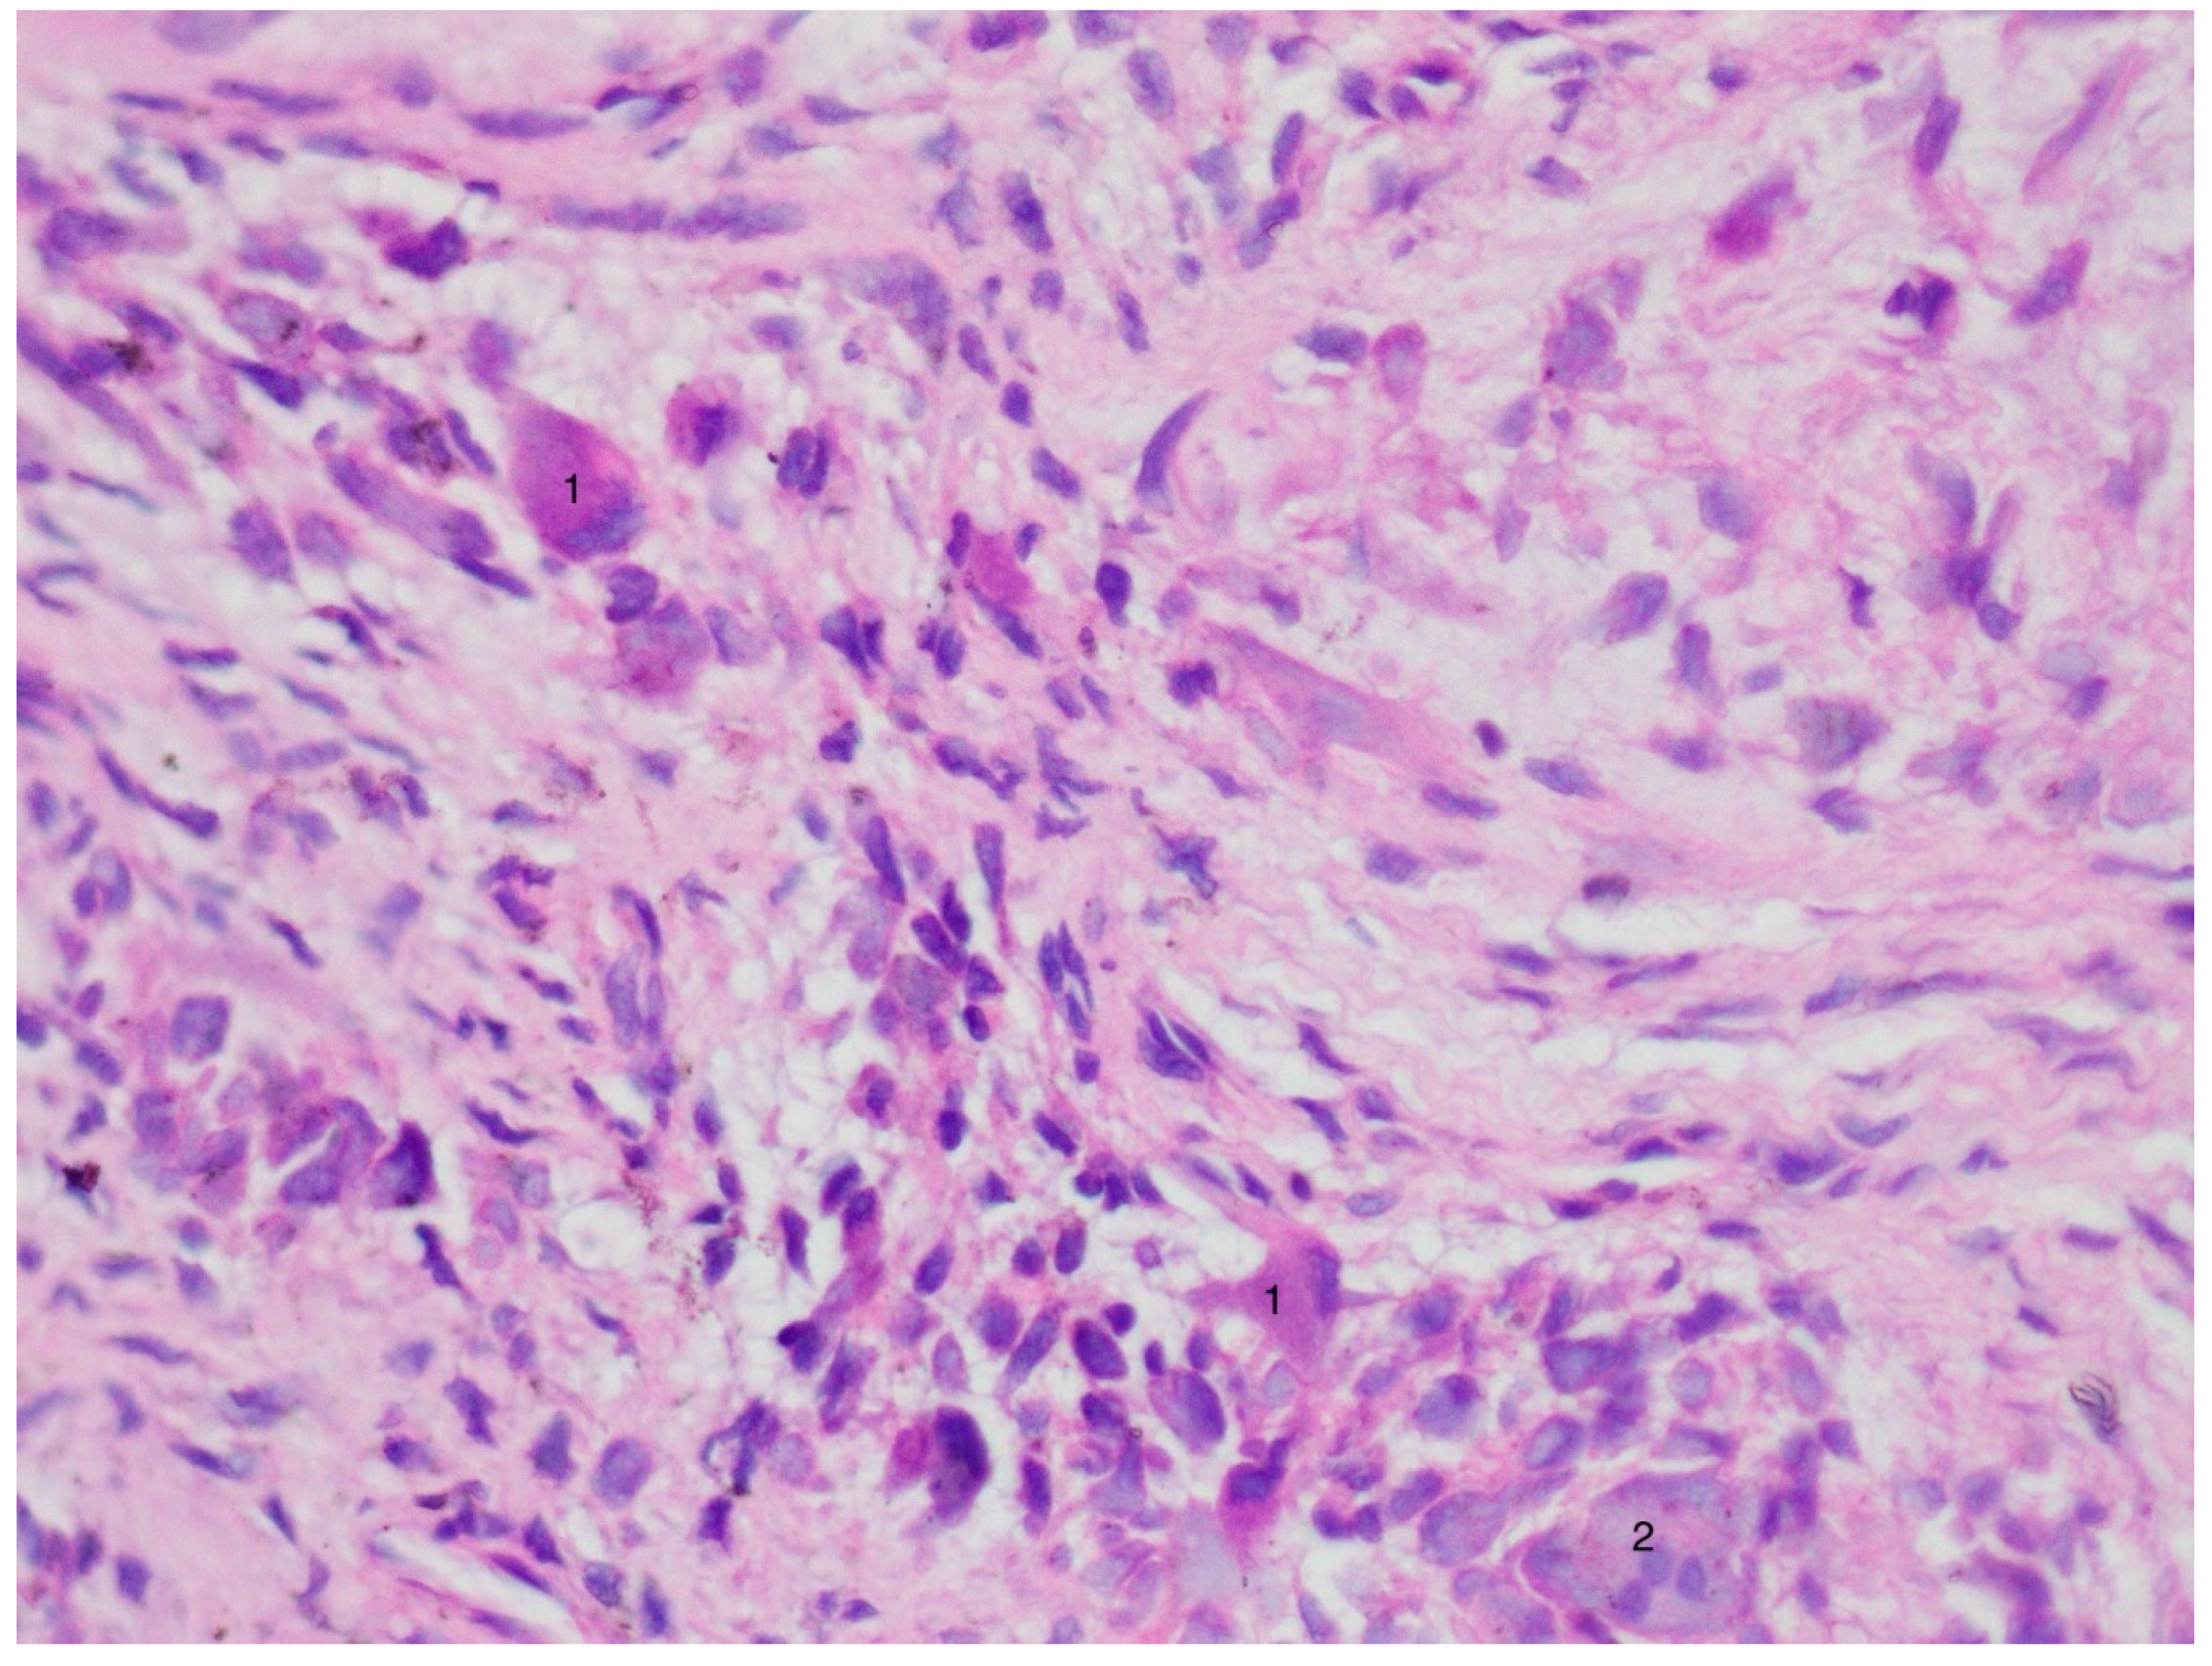

3. Results